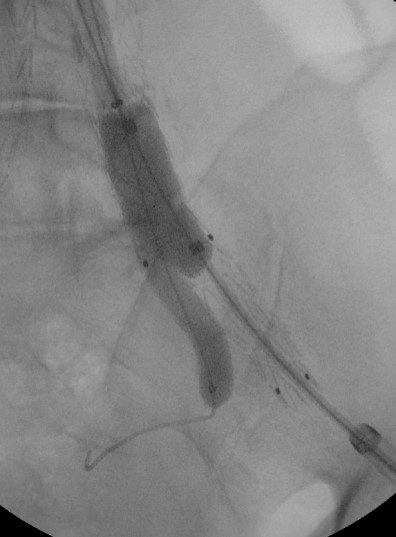

Άνδρας ασθενής 72 ετών με ανεύρυσμα κοιλιακής αορτής διαμέτρου 7 εκατοστών και ανεύρυσμα δεξιάς κοινής λαγονίου διαμέτρου 3 εκατοστών

Αντιμετωπίστηκε ενδαγγειακά με τοποθέτηση μοσχεύματος τύπου Excluder και επιπρόσθετα με την τοποθέτηση λαγονίου σκέλους με πλάγιο κλάδο δεξιά για την διάσωση της έσω λαγονίου αρτηρίας